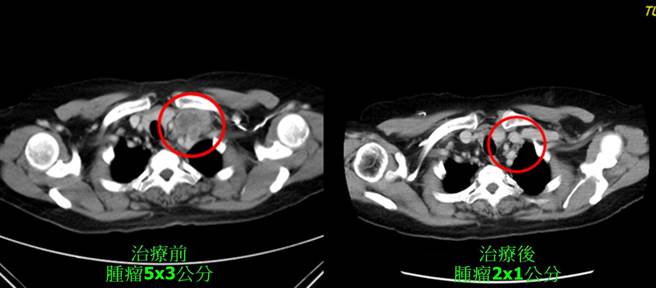

治疗前后比较图。(童综合医院提供/陈淑娥台中传真)

58岁萧姓病人7年前罹患子宫颈癌第四期,进行放射线治疗33次与化疗6次,稳定控制癌细胞,但去年癌细胞转移到颈部,童综合医院血液肿瘤科沈俊佑主任建议採行化学治疗辅助搭配肿瘤电热治疗,在进行10次后,颈部肿瘤从5x3公分缩小至2x1公分,明显见效,目前稳定治疗控制中。